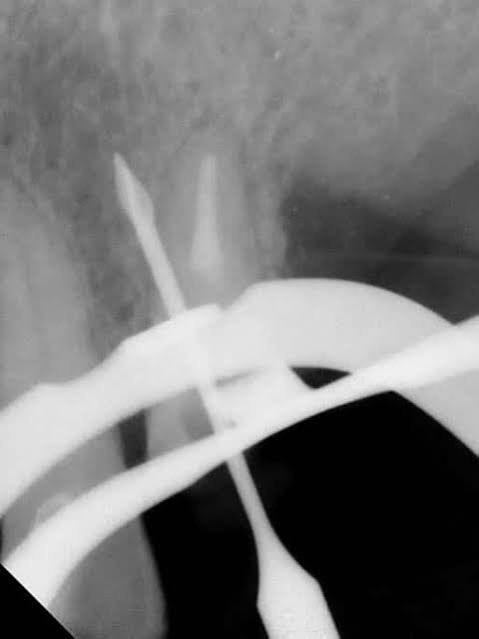

4. What type of perforation is being treated by an endodontist in this X ray?